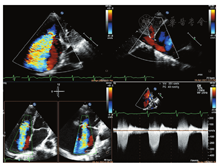

患者男,87岁,心房颤动10余年,近1年胸闷、憋喘、伴下肢水肿,不能平卧。术前经胸超声心动图(TTE)及经食管超声心动图(TEE)示:①下腔静脉宽19 mm(无呼吸塌陷率)、双房及右室增大伴轻度二尖瓣反流及极重度三尖瓣反流(tricuspid regurgitation,TR);②轻度主动脉瓣反流;③中度肺动脉高压(57 mmHg)(1 mmHg=0.133 kPa);④左室收缩功能未见异常(LVEF:63%)(图1,图2)。心电图示:心房颤动,频发室性期前收缩,ST-T改变;胸部X线示:双肺渗出,肺气肿、肺大泡,右侧胸水。CT示:三尖瓣瓣环扩大(直径:58.2 mm),右房增大(最长径:92.4 mm),下腔静脉开口增宽。临床诊断:①极重度三尖瓣关闭不全,NYHA心功能Ⅲ级;②心房颤动。鉴于该患者年龄较大以及肺气肿合并肺大泡,外科手术高危(STS评分8分,EuroscoreⅡ评分7分)症状性极重度TR,介入医生决定行经导管三尖瓣修复术。